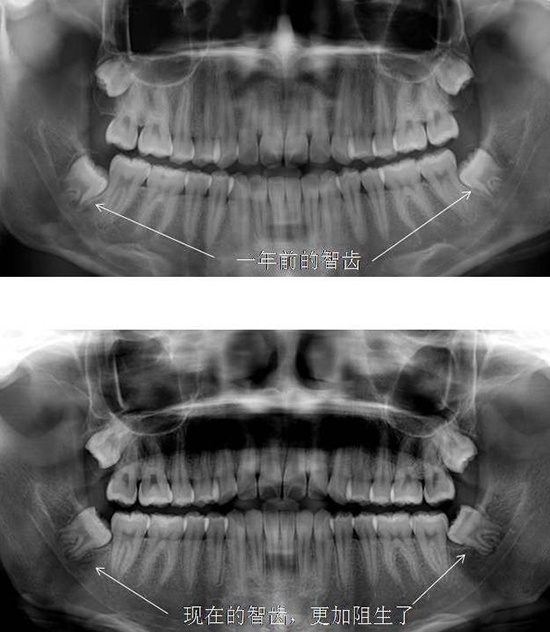

第三个case就是不听劝说,没有及早拔除智齿,以至于智齿阻生越来越严重,增加手术难度,当然病人自己术后也会更难受。

智齿的存在我们看X光片就可以预计它能否顺利萌出,如果阻生,应该尽早拔除。